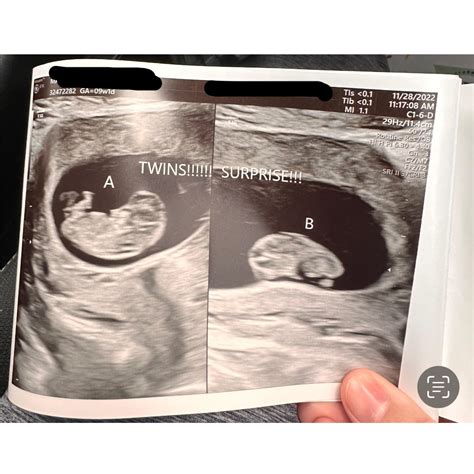

Finding Implication

Two distinct gestational sacs Indicates dizygotic (fraternal) twins.

Single gestational sac with two yolk sacs Indicates monozygotic (identical) twins.

Detectable heartbeats Confirms the viability of the embryos.

Abnormal measurements May indicate developmental issues that require further monitoring.